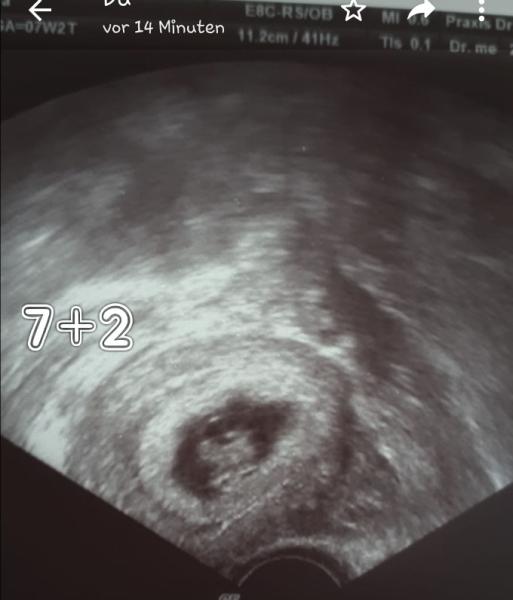

Habe ich noch nie von gehört. Aber sehr interessant Was würdet ihr bei mir sagen? Das Bild ist von 6+2 und die Plazenta liegt unter dem Baby.

UPS ich hab da glaub ich was verwechselt das unten ist der dottersack. Aber so wie das Krümelchen liegt müsste die Plazenta rechts sein. Und dann eventuell en Mädchen werden oder?

Ja sieht nach Mädchen aus wenn ich diesen ramzi richtig verstanden hab

Kann man das so ablesen oder ist das spiegelverkehrt. Weil dann muss man das anders herum sehen.